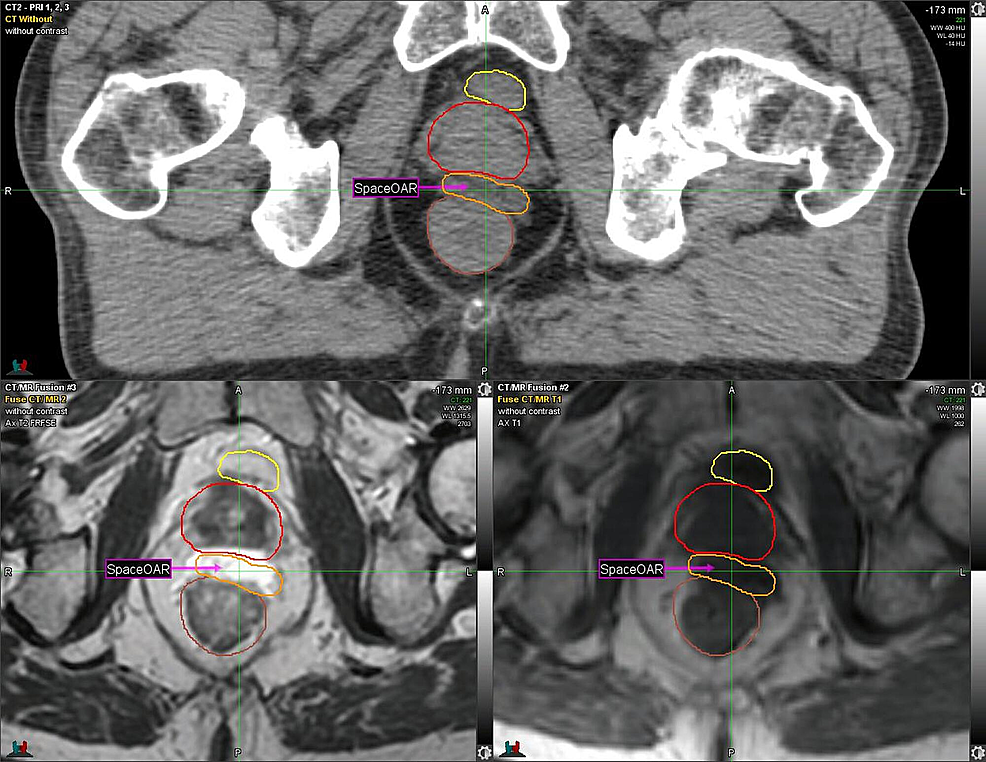

Given the patient’s history of CD, one week prior to RT, the SpaceOAR System (Augmenix; Waltham, MA) was utilized. SpaceOAR is a polyethylene glycol hydrogel that is injected into the perirectal fat and solidifies into an absorbable spacer that separates the prostate and the anterior rectal wall. Prior to spacer insertion, fiducials were placed. The hydrogel was then injected via transrectal ultrasound (TRUS) guidance with no perioperative complications and yielded a roughly 1.14 - 1.21 cm space between the anterior rectal wall and the prostate (Figure 1, Figure 2).